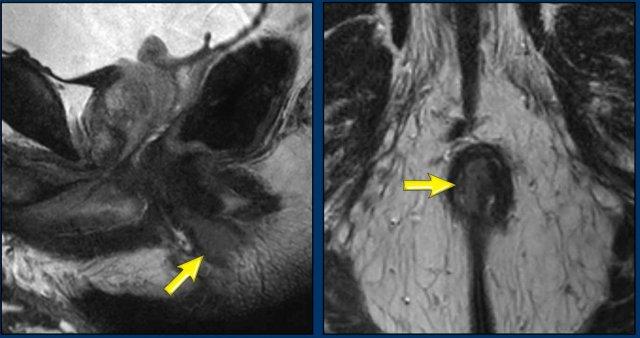

Các hình ảnh này của một bệnh nhân ung thư hậu môn.

MRI cho thấy một hạch bạch huyết to rõ rệt (đường kính trục ngắn 1,5 cm) liền kề mạch chậu trong, được phân giai đoạn là N+ trên MRI.

FDG-PET CT cho thấy tăng hấp thu FDG bệnh lý tại hạch, xác nhận đây là hạch N+.

Trong trường hợp này có hai hạch bạch huyết nhỏ trong mạc treo trực tràng được đánh giá là không rõ ràng trên MRI.

FDG-PET cho thấy tăng hấp thu FDG rõ rệt tại các hạch nhỏ này, thể hiện lợi ích bổ sung của PET so với MRI trong phân giai đoạn hạch ung thư hậu môn.

Bệnh nhân cuối cùng được phân giai đoạn là T2 N1a.